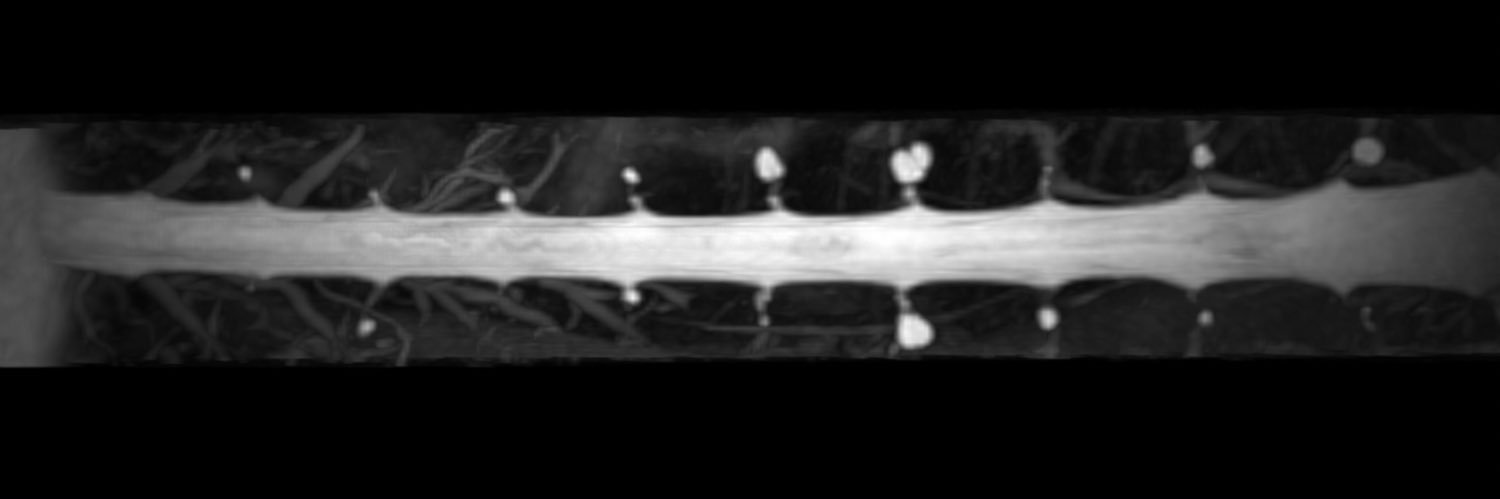

Sacral dural tears in #SIH are probably under-recognized. Why? Because the sacrum often isn’t scrutinized, or sometimes even included in the field of view on routine spine imaging. In a new multicenter @AJNR study we found: • Sacral leaks often produce isolated sacral CSF collections • Image-guided patching can lead to meaningful clinical & imaging improvement • Longitudinal imaging suggests some lesions mimicking “Tarlov cysts” may actually represent chronic or partially healed leaks Encouraging to see multicenter collaboration continue to emerge in SIH imaging/treatment research. ajnr.org/content/early/…